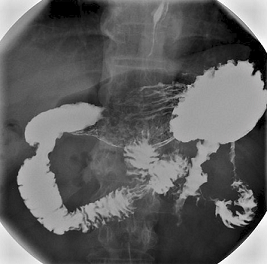

Barium-Mahlzeit

This is similar to a barium swallow. However, it aims to look for problems in the stomach and the first part of the gut (small intestine), known as the duodenum. These problems may include ulcers, small fleshy lumps (polyps), tumours, etc.

You drink some barium liquid but you then lie on a couch whilst X-ray pictures are taken over your tummy. It may take a little longer to do than a barium swallow.

So that the barium coats all around the lining of the stomach, the doctor doing the test (radiologist) may do one or more of the following:

Ask you to swallow some bicarbonate powder and citric acid before swallowing the barium. These 'fizz up' when they mix in the stomach and make some gas. (You may have the urge to burp.) The gas expands the stomach and duodenum and also pushes the barium to coat the lining of the stomach and duodenum. This makes the X-ray pictures clearer. It is the shape and contours of the lining of the stomach and duodenum which need to be seen most clearly on the pictures.

Ask you to turn over on to your stomach on the couch. Various X-ray pictures may be taken whilst you are in different positions.

You may be given an injection of a drug that makes the muscles in the stomach and gut relax.

Can I eat before a barium meal?

You will usually be asked not to eat anything for several hours before this test. (Food particles in the gut can make it difficult to interpret the X-rays). However, you may be allowed sips of water up to two hours before the test.

Barium meal stomach X-ray

By Lucien Monfils (Own work) via Wikimedia Commons